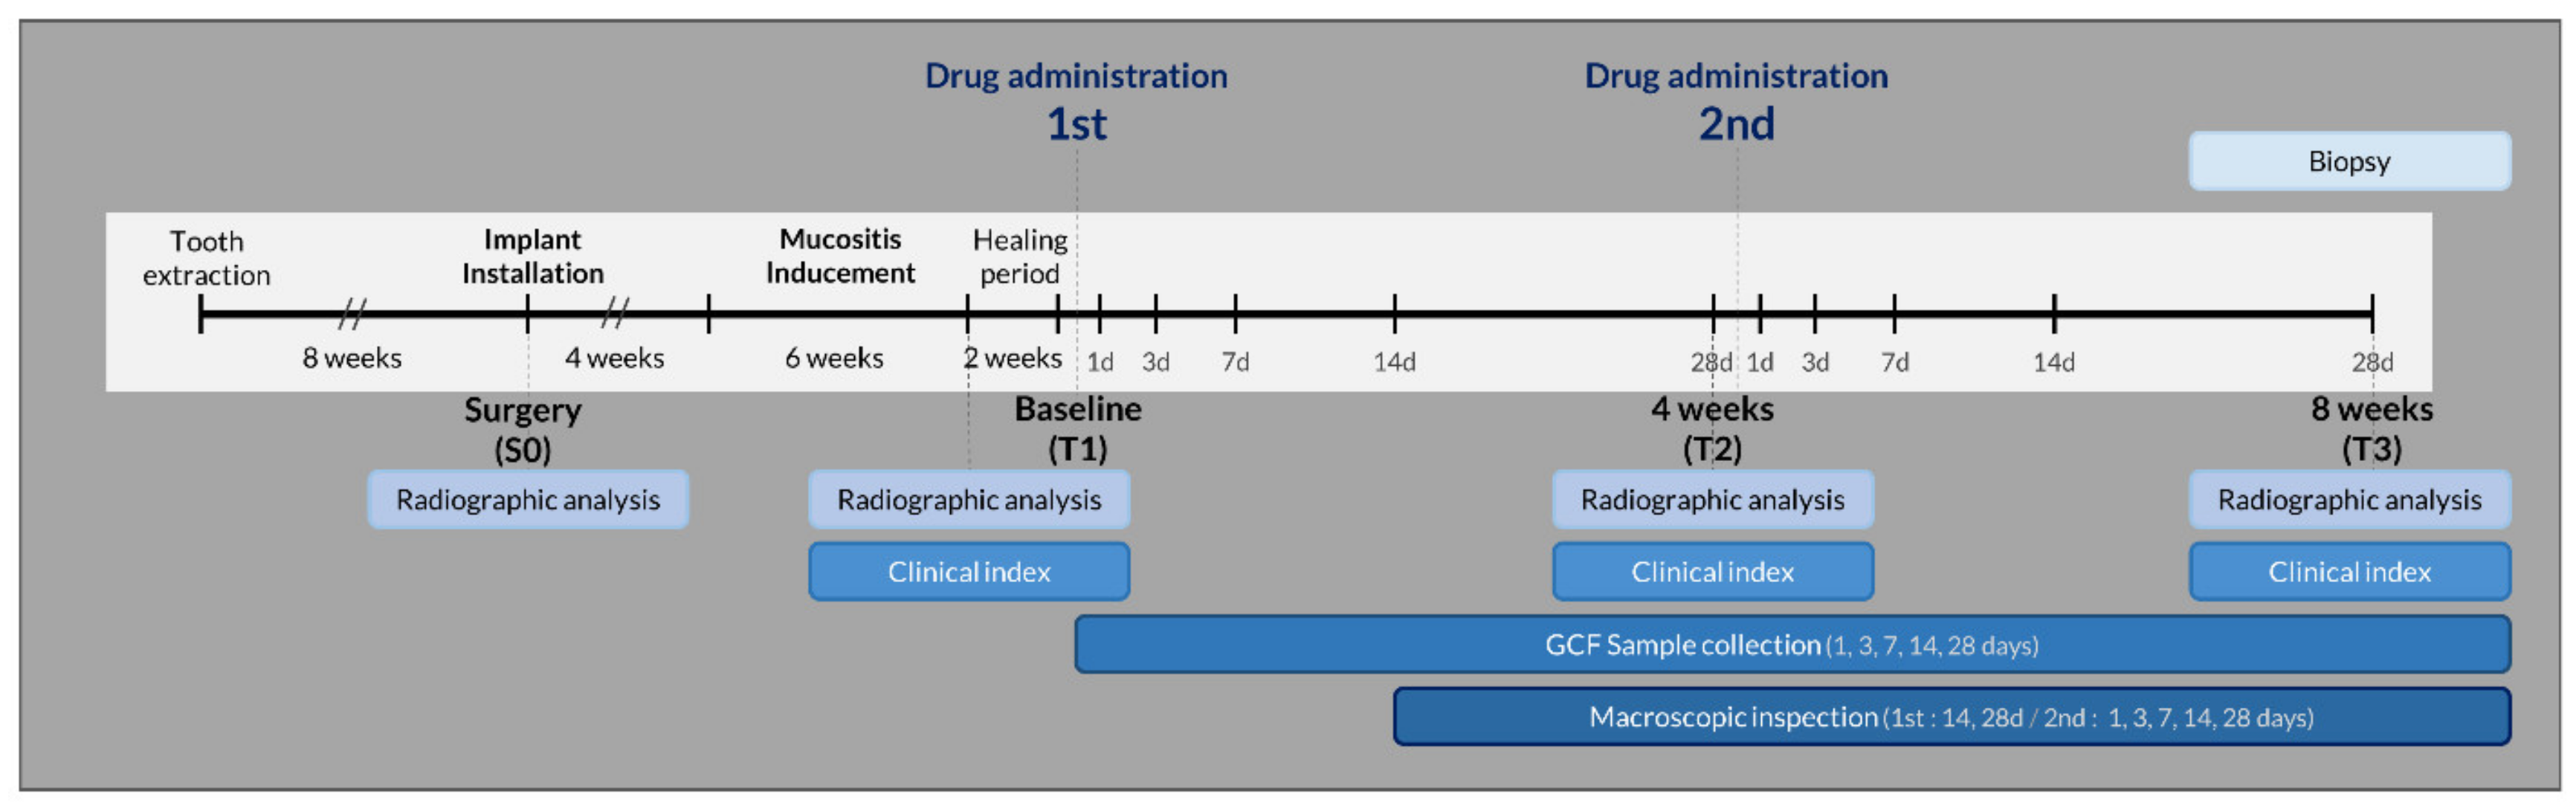

2.2. Study Design

2.3. Experimental Procedures

2.3.1. Tooth Extraction and Implant Installation

2.3.2. Experimental Peri-Implant Mucositis

2.3.3. Antimicrobial Interventions